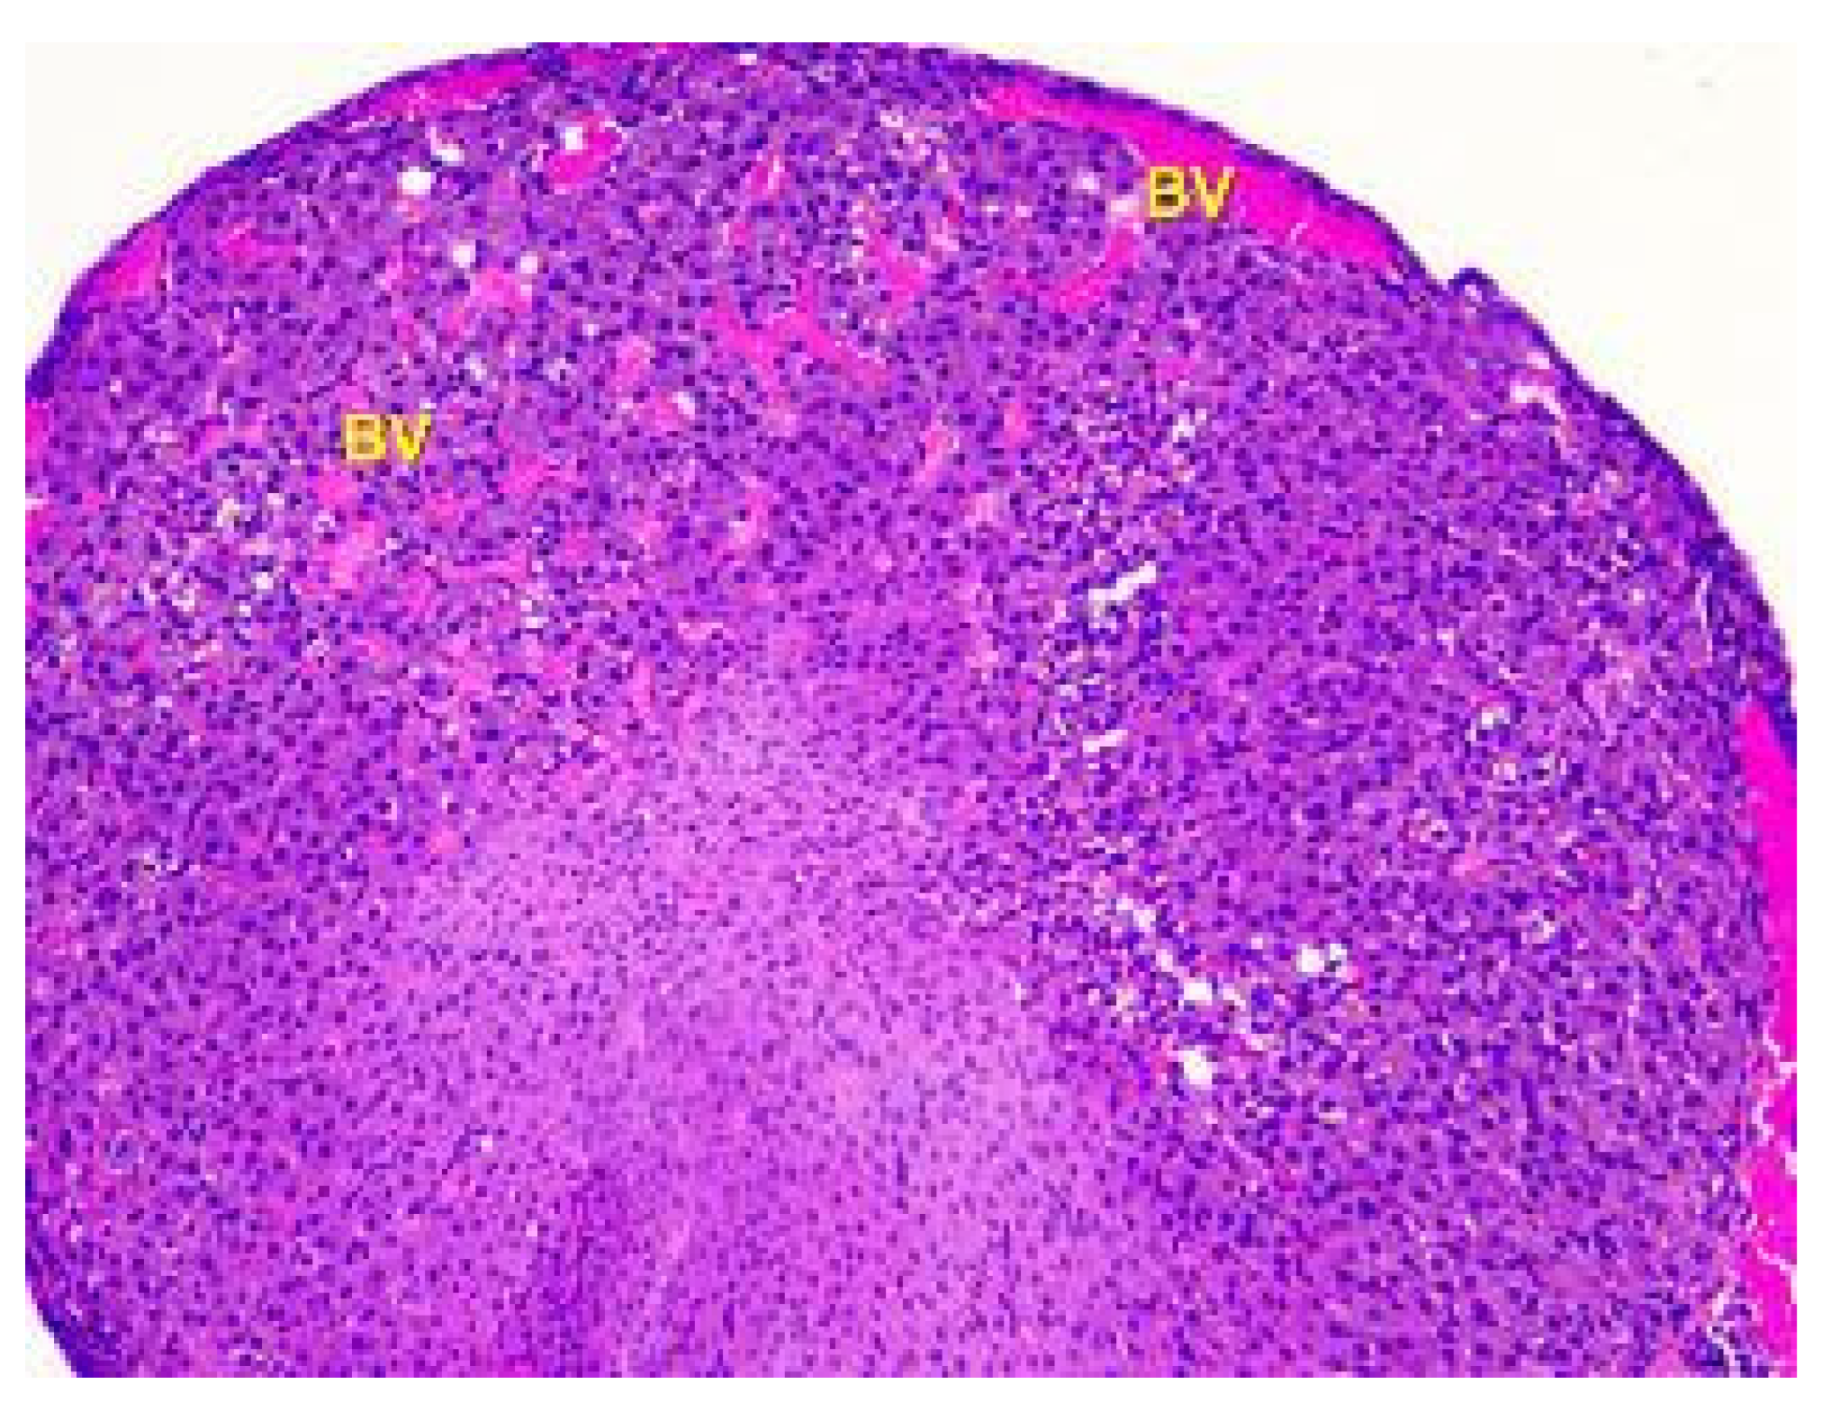

- Denefil, O.V.; Bilyk, Y.O.; Chorniy, S.V.; Fedoniuk, L.Y.; Chornii, N.V. The peculiarities of morpological changes of rats’ ovary and biochemical state under the damage with different doses of lead acetate. Wiad Lek. 2022, 75, 377–382. [Google Scholar] [CrossRef] [PubMed]